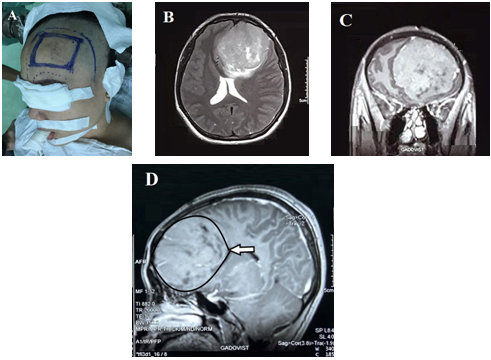

Khám lâm sàng: Bệnh nhân có định hướng về thời gian, địa điểm và con người nhưng lại kém chú ý và tập trung với khả năng phán đoán kém. Điểm kiểm tra trạng thái tâm thần là 25/30. Huyết áp: 120/70 mmHg, nhịp tim: 70 nhịp/phút. Khám thần kinh, bao gồm cả dây thần kinh sọ và khám toàn thân khác, đều không ghi nhận bất thường. Kết quả xét nghiệm máu trong giới hạn bình thường. Chụp cộng hưởng từ (MRI) sọ não cho thấy một tổn thương tăng tín hiệu rõ ở vùng trán bên trái có kích thước 65x70x70 mm, ranh giới đều, có sự chèn ép nhu mô não lân cận với phù não xung quanh, sau khi tiêm, khối u ngấm thuốc cản quang khá đồng nhất, bên trong có dịch hoại tử không thấm cản quang. Khối u đè đẩy sừng trán não thất bên hai bên, đường giữa di lệch sang phải #23mm, chèn nhẹ chéo giao thị. Những đặc điểm này phù hợp với u màng não thùy trán trái khổng lồ (Hình 1).

Hình 1. Hình 1A. Chuẩn bị bệnh trước mổ, đánh dấu vị trí mổ với u màng não thùy trán trái khổng lồ. Trên phim cộng hưởng từ có thuốc cản quang Hình 1B-1C-1D (mặt phẳng cắt ngang, cắt dọc đứng, cắt dọc ngang) Khối u vùng trán bên trái có kích thước 65x70x70 mm, ranh giới đều, có sự chèn ép nhu mô não lân cận với phù não xung quanh, sau khi tiêm, khối u ngấm thuốc cản quang khá đồng nhất, bên trong có dịch hoại tử không thấm cản quang. Khối u đè đẩy sừng trán não thất bên hai bên, đường giữa di lệch sang phải #23mm